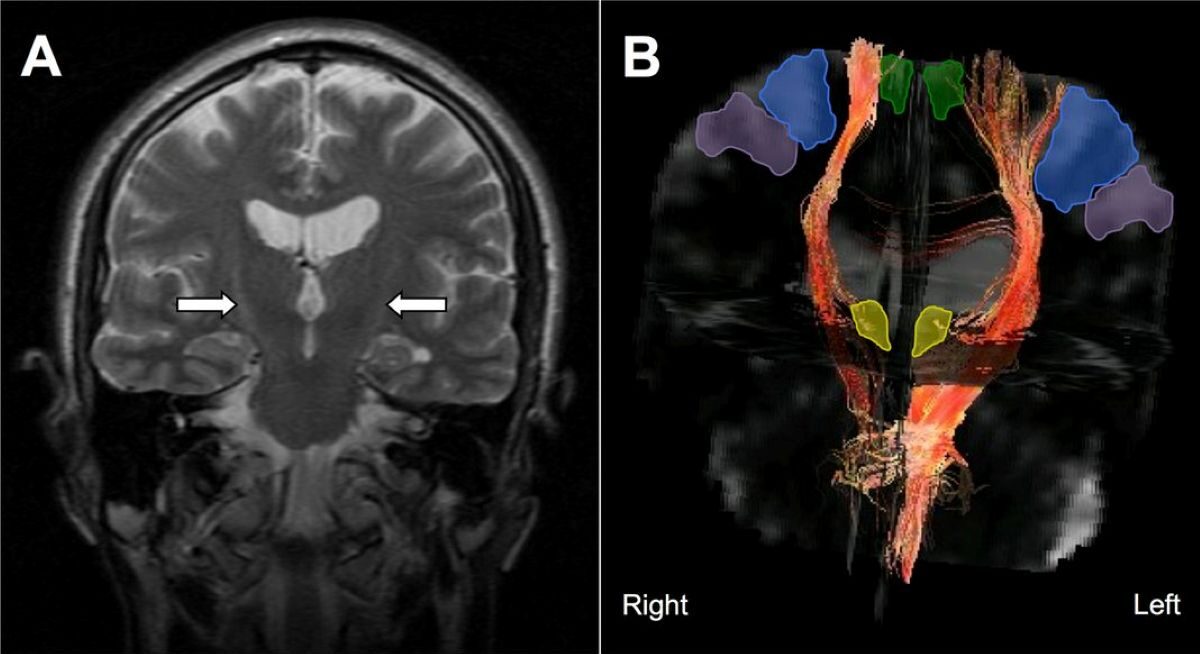

- EEG signals suggested improved brain activity patterns associated with ALS.